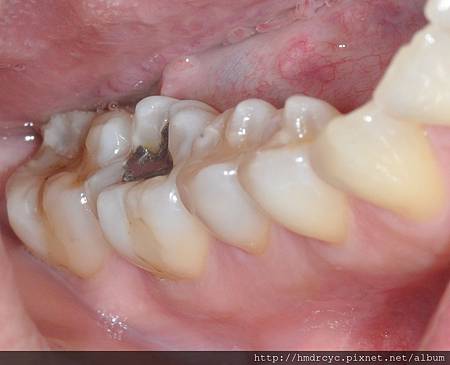

銀粉填補已產生二次蛀牙

前金的L小姐有相同問題

初診檢查發現

下排大臼齒銀粉填補已產生二次蛀牙

討論後決定同時改變牙齒外觀

去除銀粉改為樹脂美觀填補